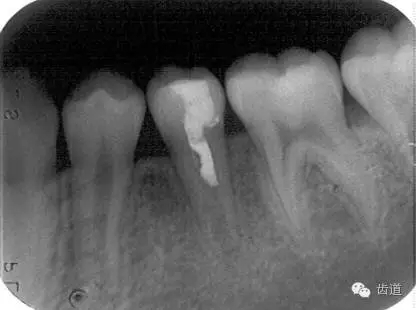

術(shù)后三個(gè)月

術(shù)后六個(gè)月

術(shù)后兩年